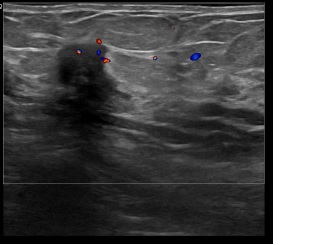

아산유외과개원후 831번째 유방암진단

상기환자는 만져지는 멍울로 내원하신 60대초반

여성분으로 의심스러운 우측혹 조직검사 시행해 유방암으로 진단되었습니다